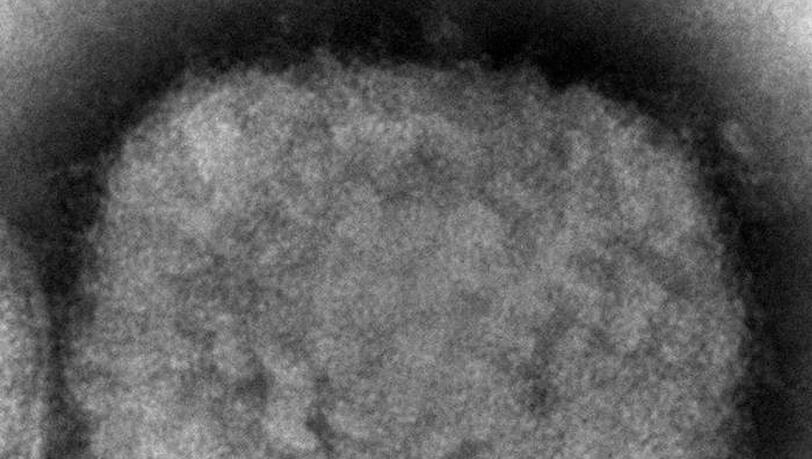

In den vergangen Tagen waren in mehreren westlichen Ländern einige Fälle der dort eigentlich sehr selten auftretenden Infektionskrankheit nachgewiesen worden. Der Charité-Infektiologe Leif Sander beschrieb die Affenpocken bei Twitter als weniger krankmachend als die Pocken, es sei aber "dennoch eine ernste und in Einzelfällen tödliche Erkrankung". Laut RKI gehören sexuelle Handlungen zu einem der möglichen Übertragungswege.